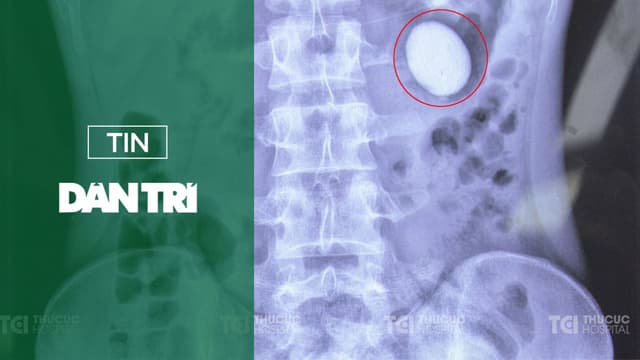

Báo điện tử Dân Trí đưa tin về bài viết “Hy hữu sỏi có hình dạng như quả trứng xuất hiện ở thận của chàng trai 22 tuổi” ngày 15/11/2024. Để cập nhật thông tin tới khách hàng, chúng tôi sẽ trích nội dung từ Báo Dân Trí để cung cấp tới bạn đọc. [Trích […]